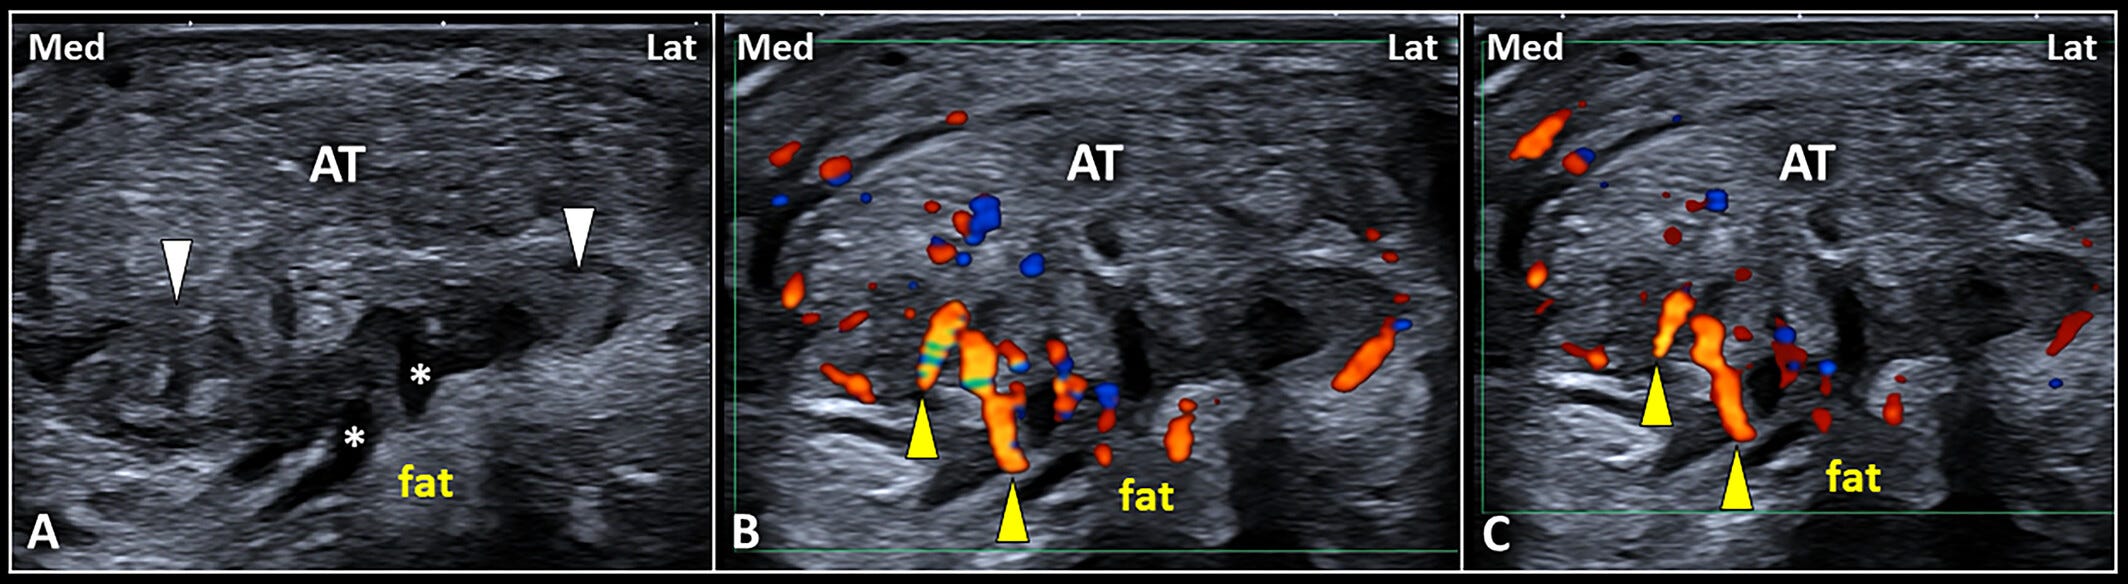

Patrones ecográficos de hipertrofia de la bursa retrocalcánea.

Mediante un corte transversal (A), pueden visualizarse con precisión el derrame anecoico (asteriscos blancos) y la hipertrofia sinovial hipoecoica (puntas de flecha blancas) de la bursa retrocalcánea (RCB), situadas por debajo de la porción insercional del tendón de Aquiles (AT).

De forma interesante, se observa hipervascularización (puntas de flecha amarillas) que afecta principalmente a la porción medial de la RCB, respetando su receso lateral, como se muestra en (B y C).

Lat: lateral; Med: medial.

La imagen transversal también permite inclinar suavemente el transductor en diferentes ángulos para aprovechar el fenómeno de la anisotropía, mejorando así el contraste entre la grasa de Kager y el tejido sinovial hipertrofiado. Este ajuste fino es lo que permite al ecografista “ver” más allá de lo evidente, como cuando Batman activa el modo detective en su visor y de pronto la escena cobra una nueva dimensión.